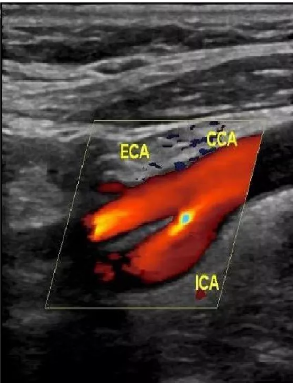

心血管超声

贯穿生命始终的心血管超声:先天性心脏病(胎儿期、小儿期、成人期)、冠心病、心脏瓣膜病、心力衰竭、血管......